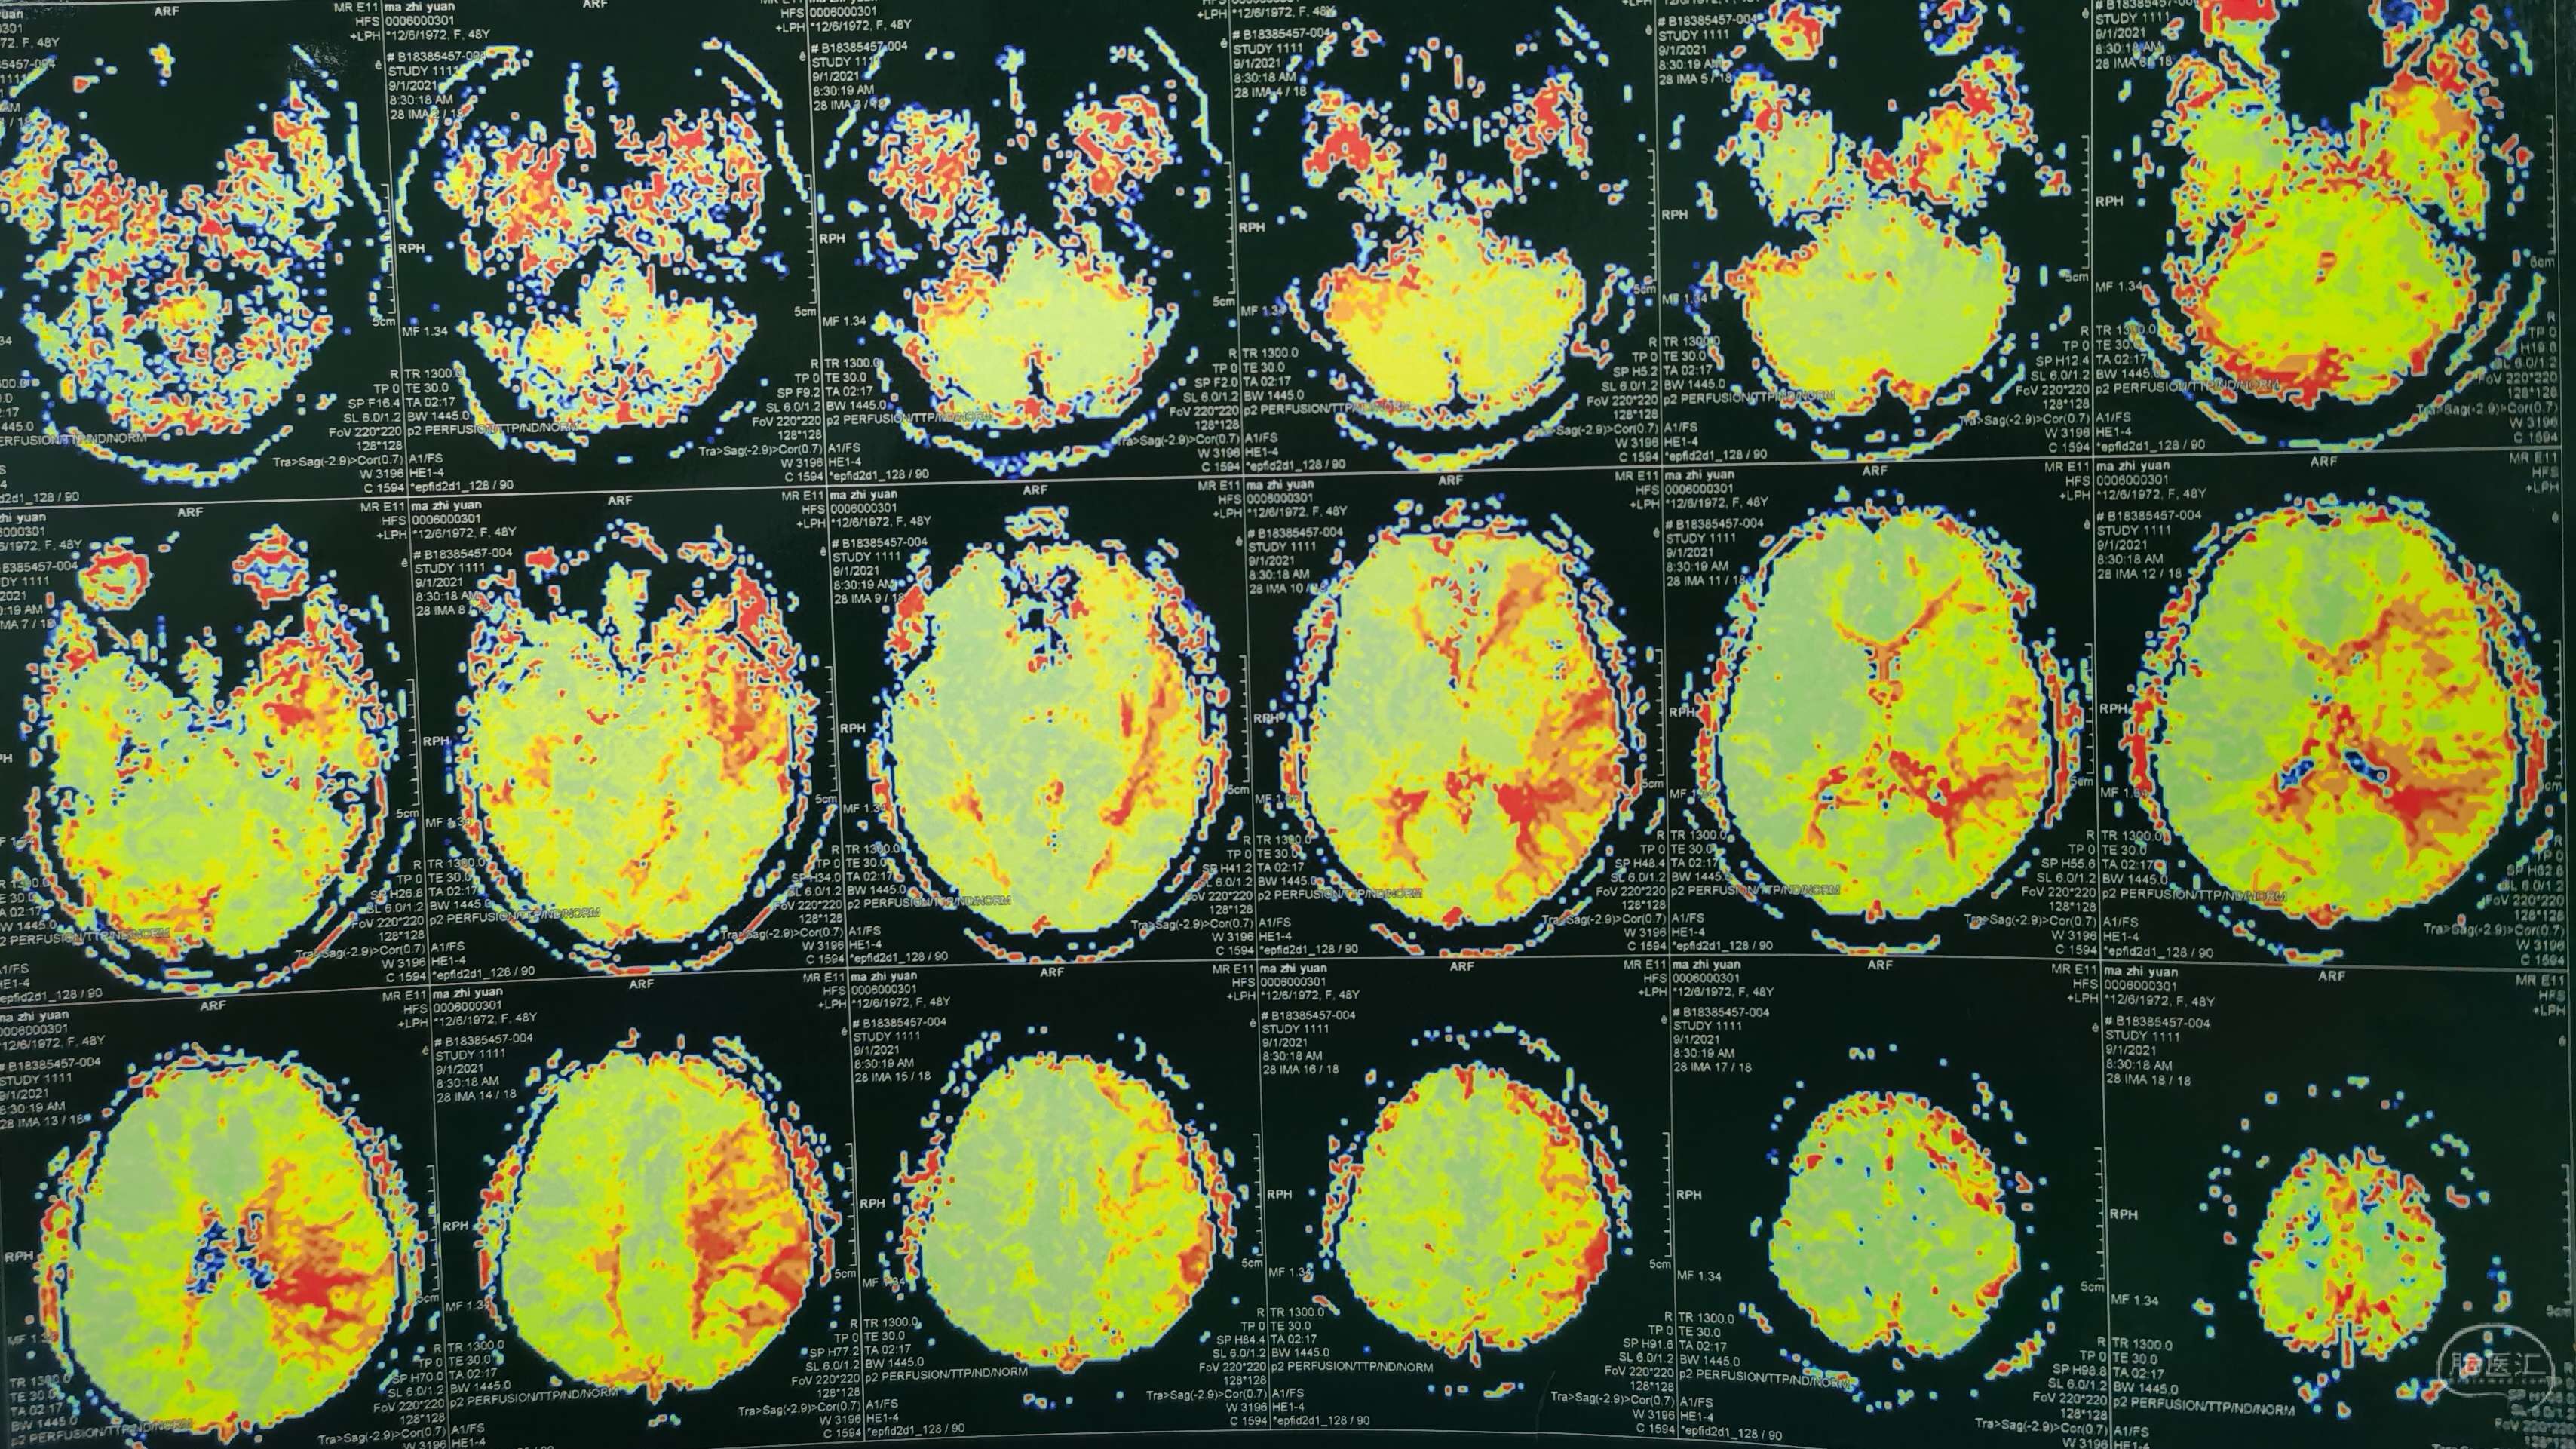

磁共振灌注提示:双侧大脑半球低灌注改变。